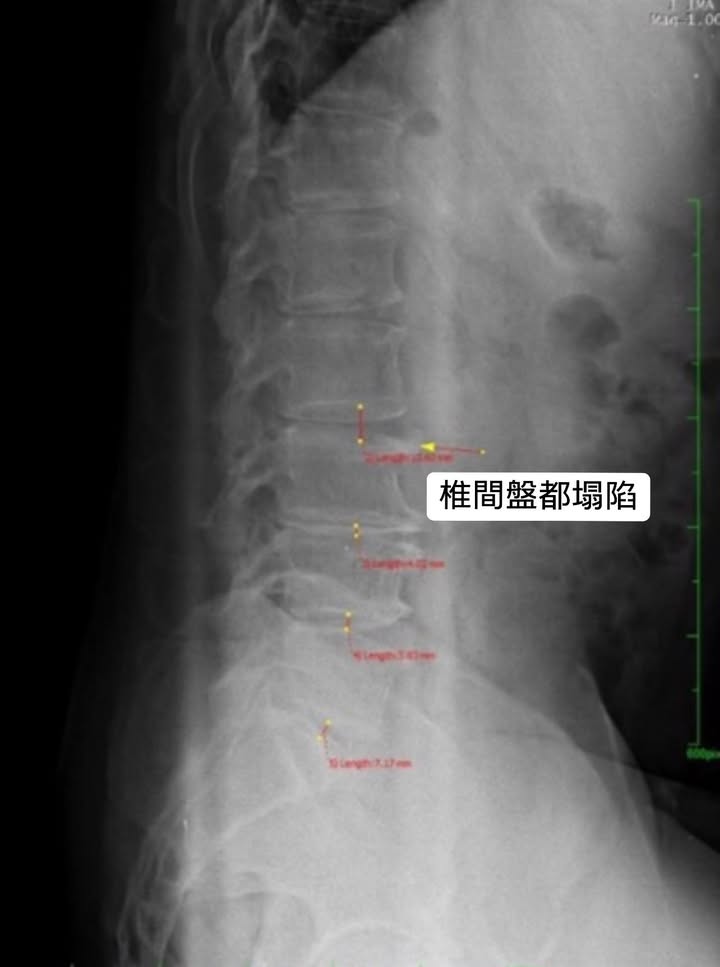

💢醫案:門診中的桃園平鎮詹先生因為嚴重椎管狹窄,來診前已經寸步難行,伴隨強烈下肢麻痛,讓他四處找醫生,但效果都不如預期,原本想說要去開刀了,經過友人介紹來台北就醫諮詢